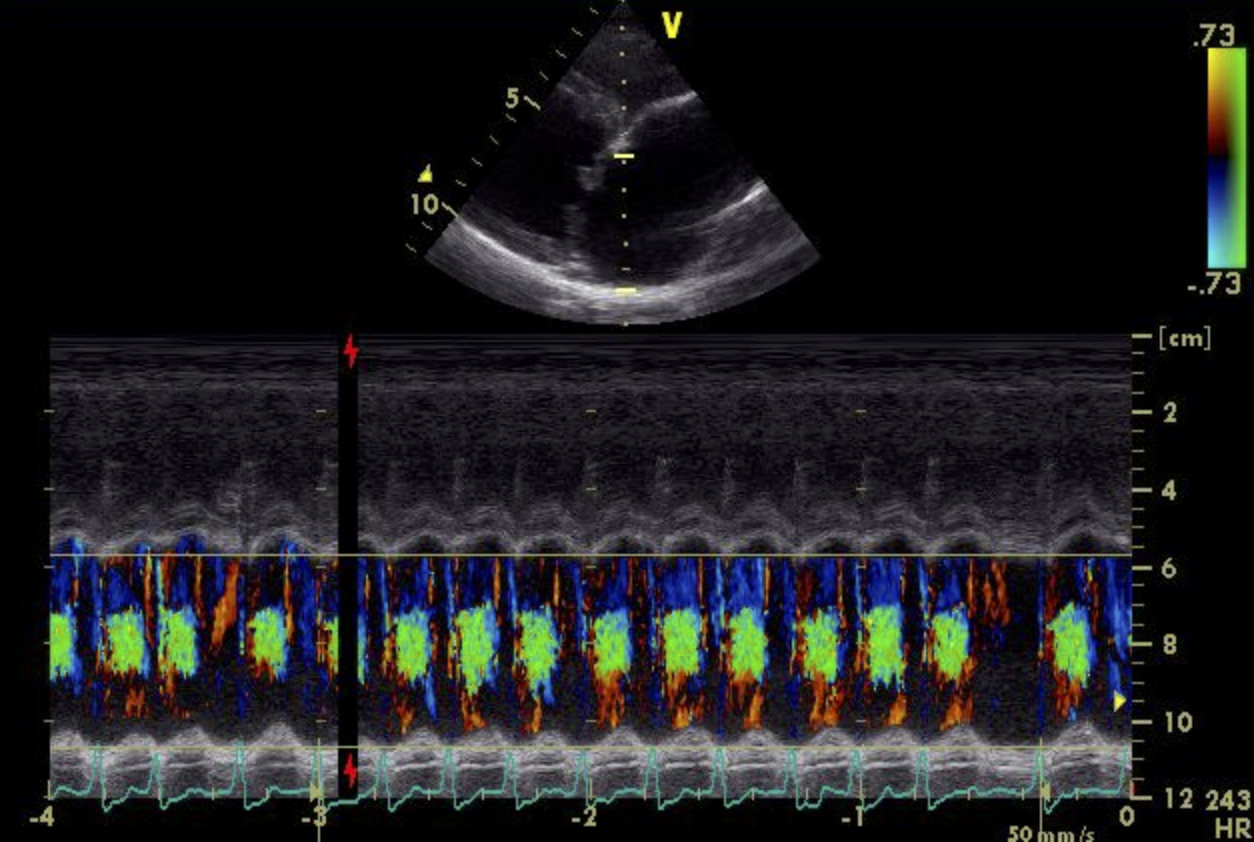

Die Ultraschalluntersuchung des Herzens zeigt letztendlich die Ursache der Veränderungen: Bubbles Herzklappe zwischen dem linken Vorhof und der linken Herzkammer, die Mitralklappe, schließt sich nicht mehr vollständig. Das EKG bei Bubbles ist in Ruhe unauffällig.